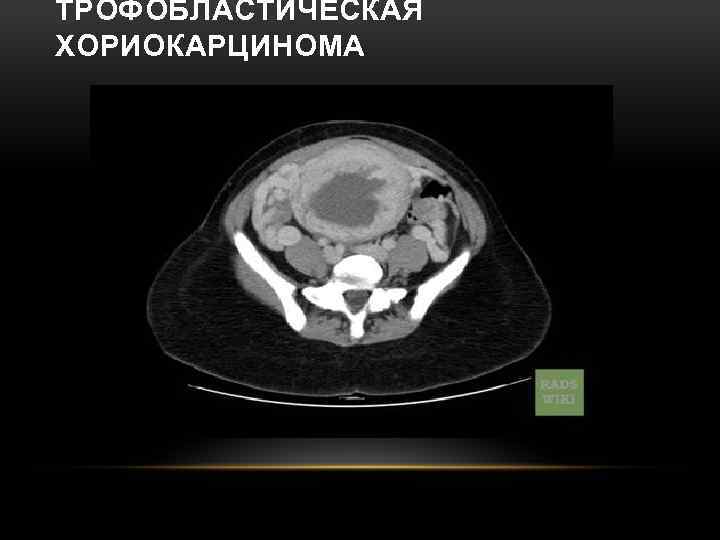

ТРОФОБЛАСТИЧЕСКАЯ ХОРИОКАРЦИНОМА • представлена смешанной структурой из эпителия трофобласта с элементами цито-, синцитиотрофобласта и клеток промежуточного звена, ворсинки отсутствуют • Опухоль характеризуется быстрой и глубокой инвазией в окружающие ткани и стенки сосудов. • Быстрый рост опухоли сопровождается обширными центральными некрозами с сохранением по периферии жизнеспособных клеток

ОСОБЕННОСТИ ТРОФОБЛАСТИЧЕСКОЙ ХОРИОКАРЦИНОМЫ: • встречается 1: 20 000 беременностей • высокая частота метастазирования в отдаленные органы (легкие, влагалище, органы малого таза, печень, головной мозг, селезенка, желудок, почки) • первые клинические симптомы — кровотечение или обнаружение отдаленных метастазов • высокая чувствительность к химиотерапии • прогноз: излечение в 90% наблюдений

ТРОФОБЛАСТИЧЕСКАЯ ХОРИОКАРЦИНОМА